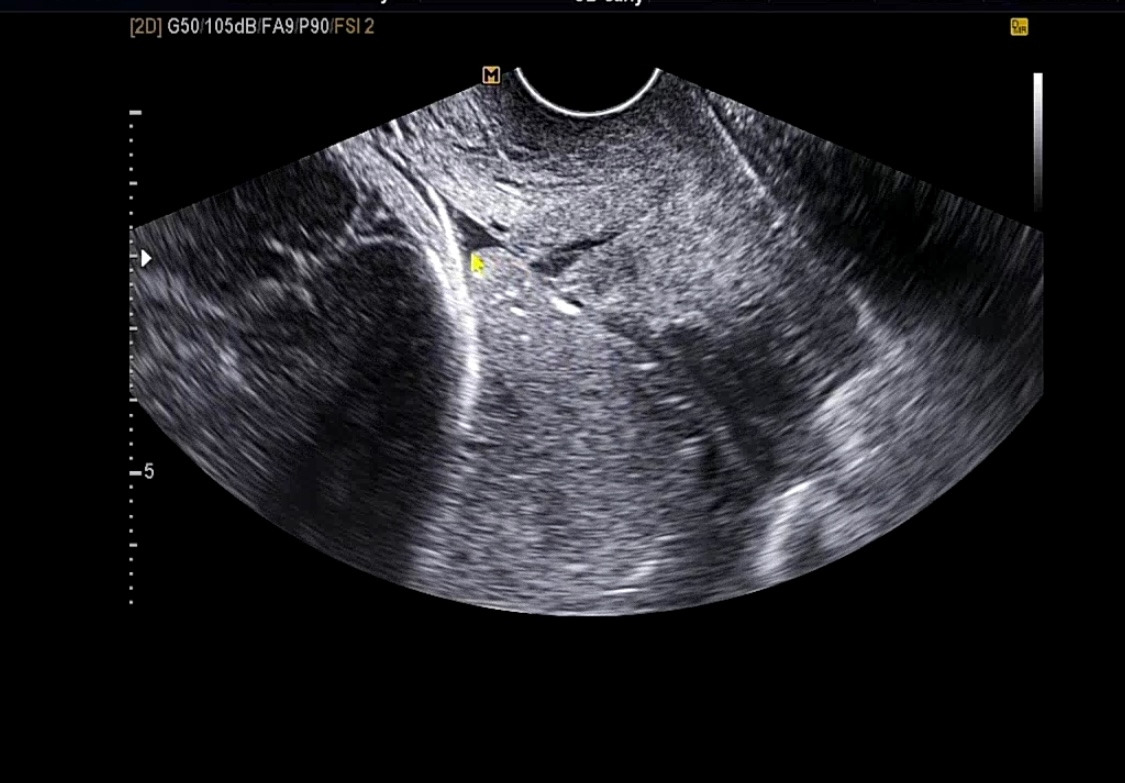

전치태반이기 때문에 경부 길이를 나는 질 초음파로 측정한다. 그리고 태반이 덮고 있는지 확인을 한다.

이 병원에서는 부분 전치태반이라고 하셨다. 살짝 덮고 있다고..

혹시 그사이 조금 올라간 건가? 이제 배가 살짝 나오기 시작했는데 그래서 조금 올라간 거가?라는 생각이 들었고 제발 그다음 대학병원 방문 시 산모님! 전치태반 이제 아니네요!!라는 소리를 너무너무 듣고 싶다.

그게 안되면 태반이 올라가서 부분 전치태반이에요!라는 소리만이라도...!